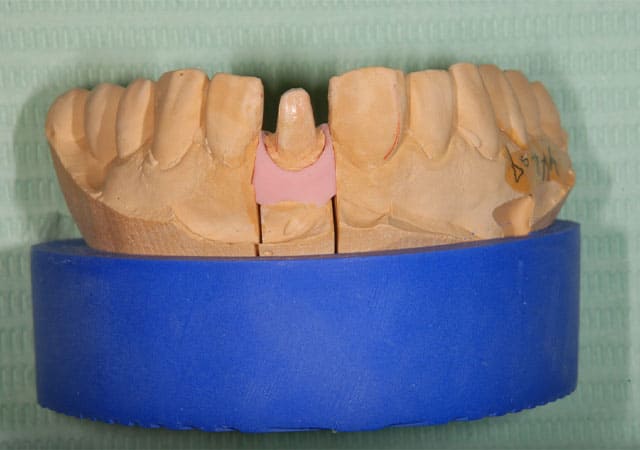

仮歯に置き換え、見た目の確認をしてもらいました。

反対側に近い形となっており、元々の歯よりも大きいため、全体的に小さくしてほしいとの希望でした。

患者さんの希望を反映した補綴物が完成しました。